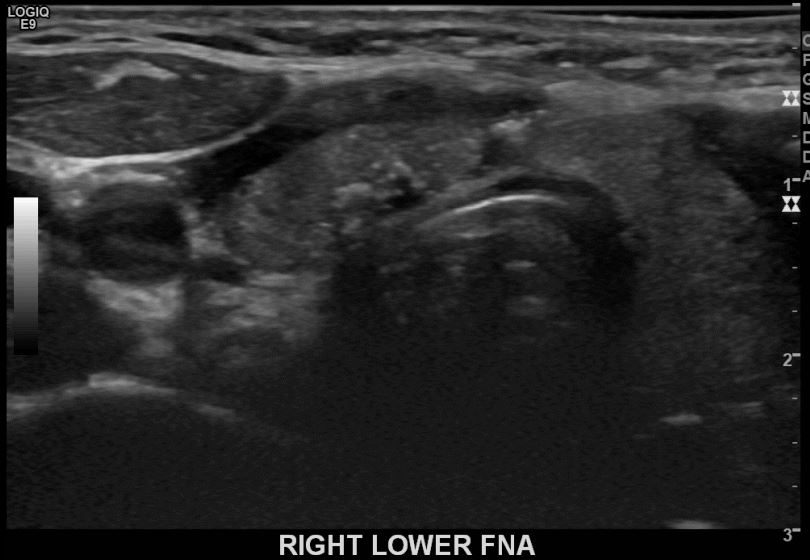

상기환자 외부검사이상소견으로 내원하신 30대 초반 여성분으로 의심스러운 우엽혹 세포검사진행후 갑상선암으로 진단되었습니다